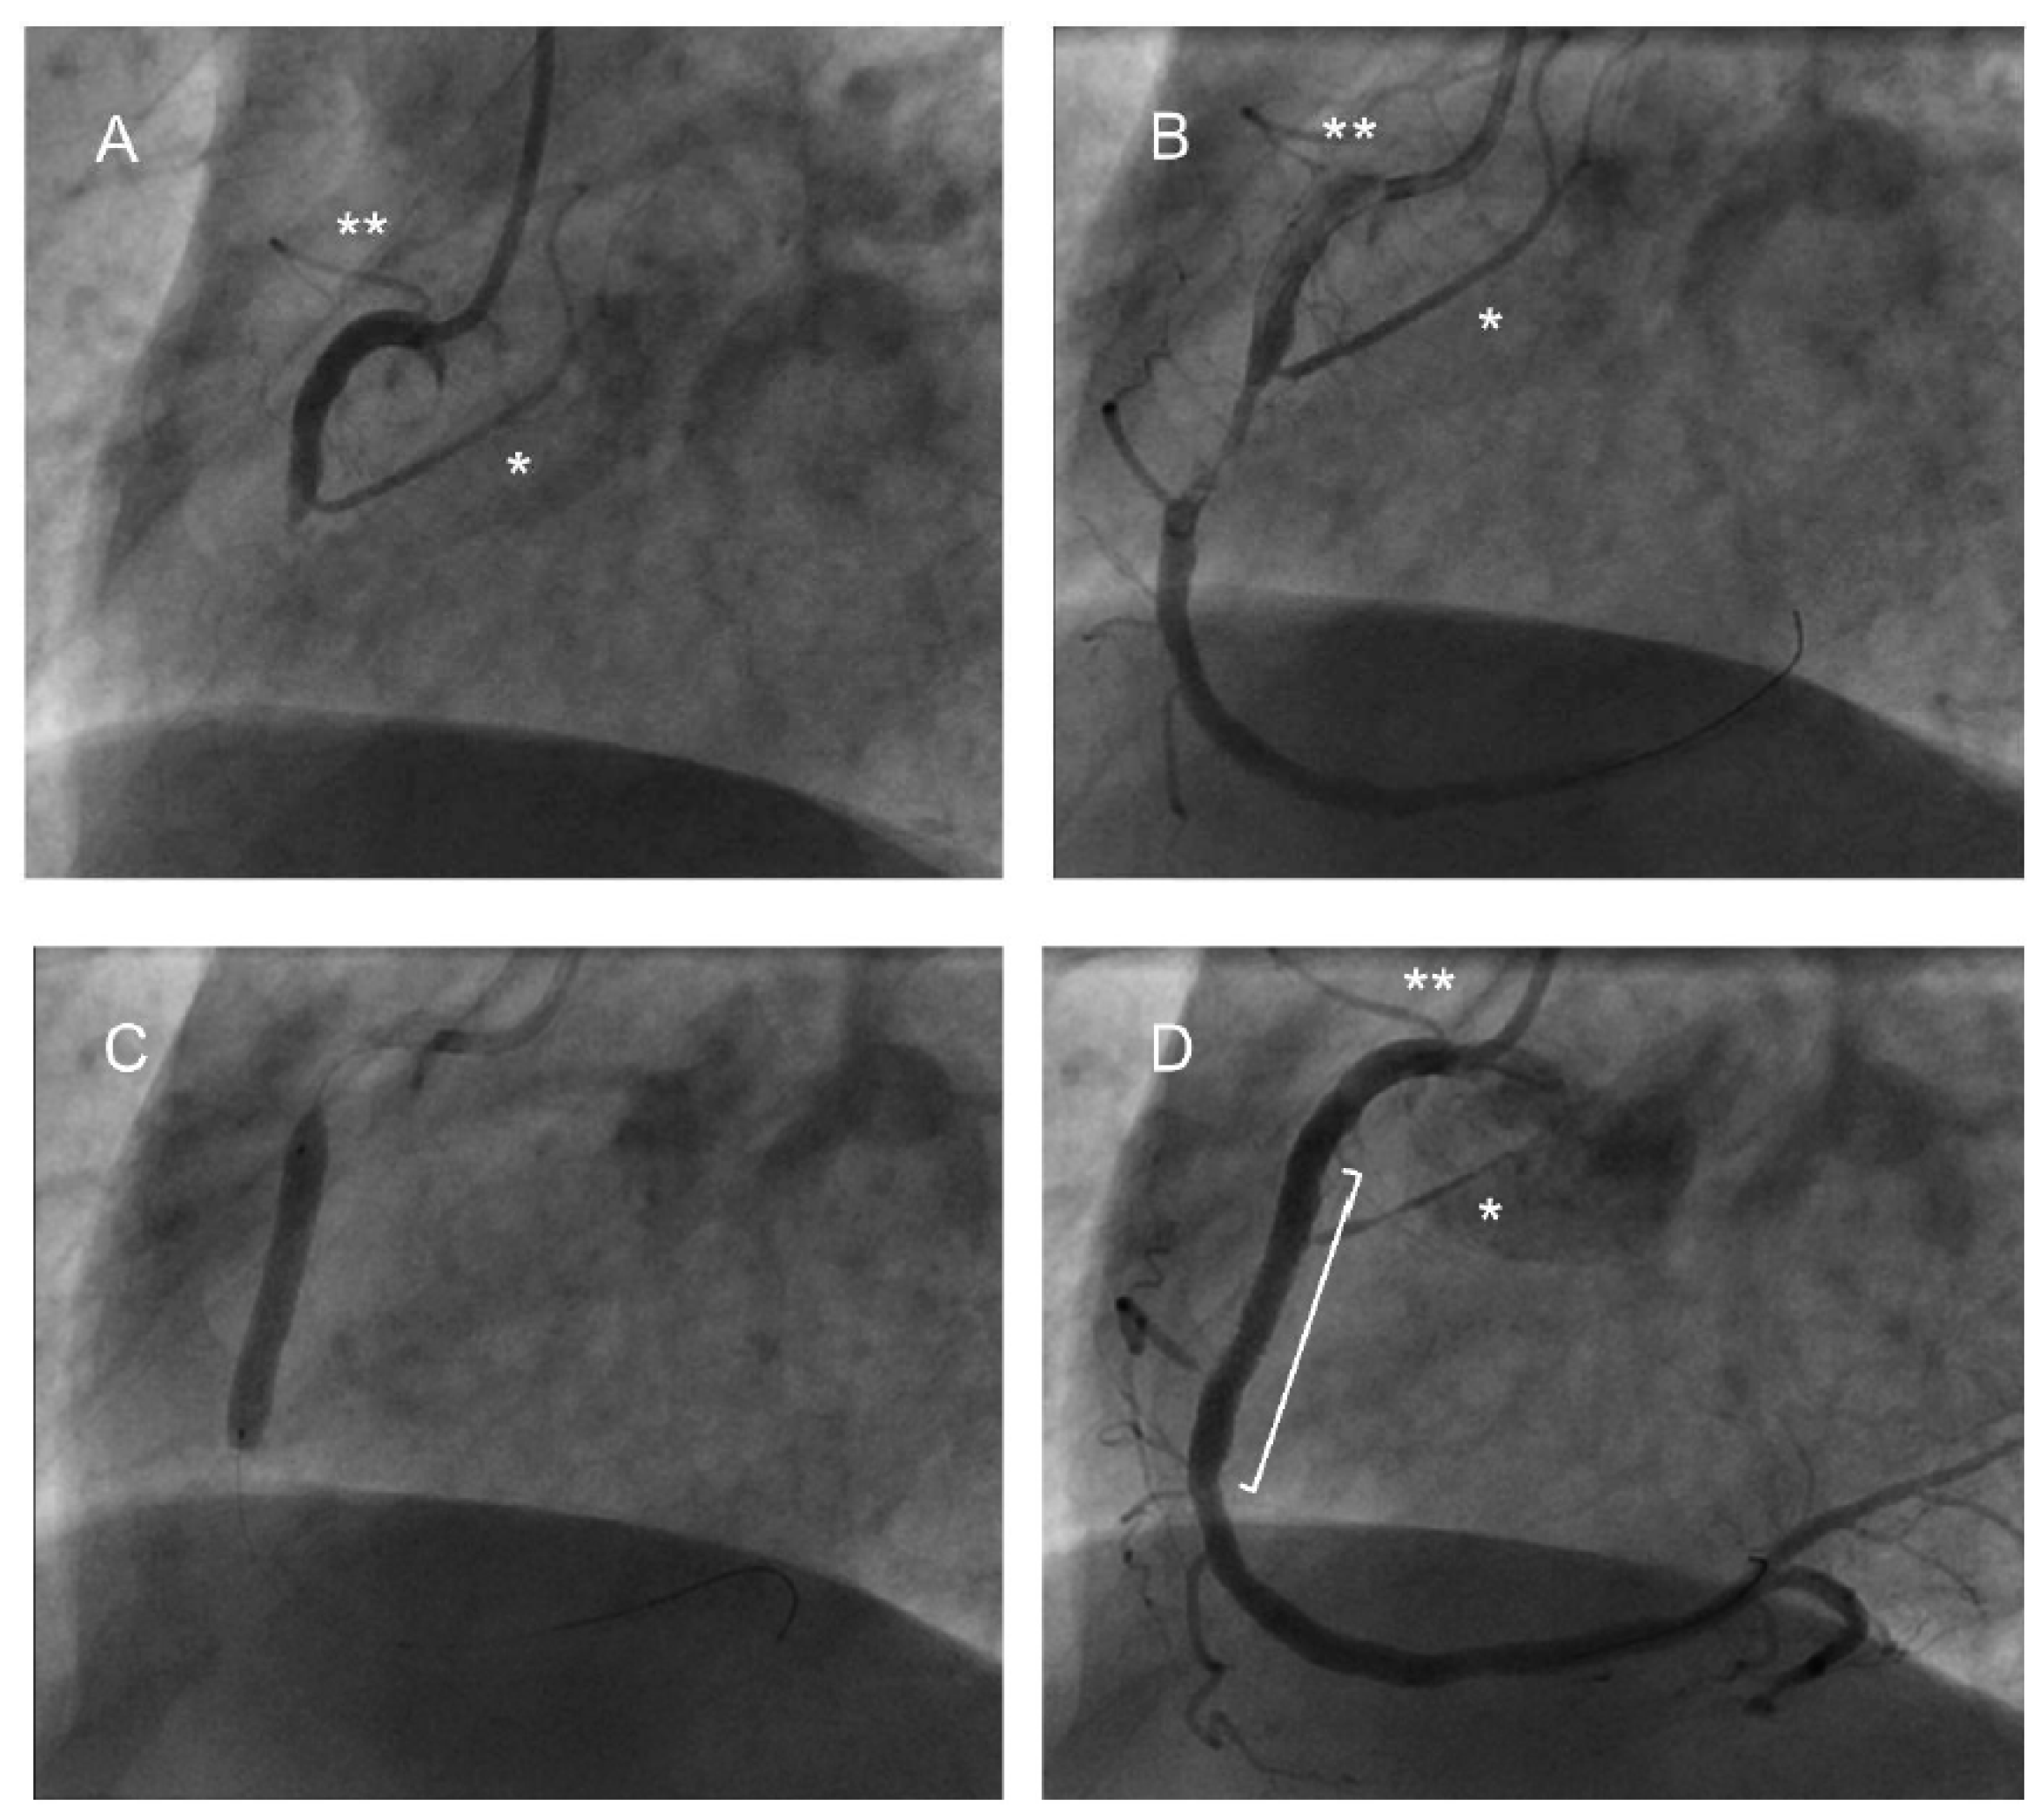

3.3. Coronary Angiogram Findings

3.4. Cardiac Intervention